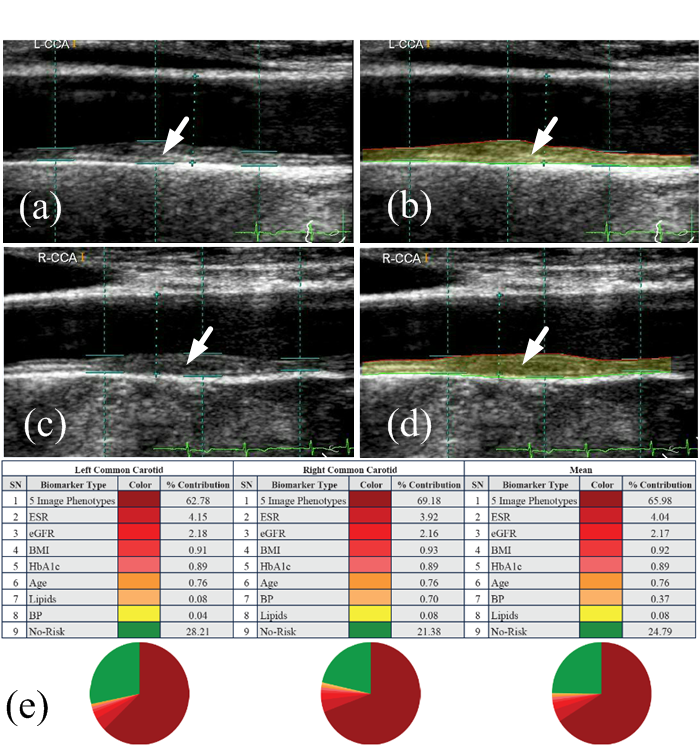

The AECRS2.0 is an integrated risk prediction algorithm that is comprised of 13 predictors, including 5 carotid ultrasound image-based phenotypes [128]. The independent contribution of each risk predictor in the 10-year CVD risk is shown in Fig. 9 and is preferred as a preventive screening tool [35]. This tool has been applied to the bulb region and correlated to renal scores [50, 180, 181, 182] or rheumatology patients [183].

Fig. 9.

Fig. 9.Independent contribution of risk predictors in the 10-year CVD risk profile of a patient estimated for the left common carotid artery, right common carotid artery, and mean of left and right common carotid artery [AtheroEdge™ 2.0]. (a,b) Original and reproduced ultrasound scans for moderate-risk patient. (c,d) Original and reproduced ultrasound scans for high-risk patient. (e) Independent contribution of risk predictors in the 10-year CVD risk. The figure was reproduced with permission [46] (courtesy of AtheroPoint, Roseville, CA, USA).